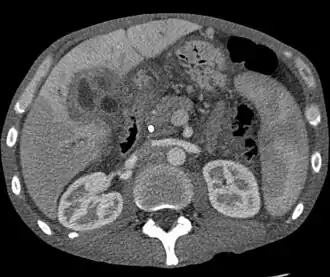

A ultrassonografia do fígado e das vias biliares é frequentemente usada como modalidade de imagem inicial em pacientes com suspeita de icterícia obstrutiva.[48][49] O ultrassom pode identificar obstrução e dilatação ductal e, em alguns casos, pode ser suficiente para diagnosticar o colangiocarcinoma.[50] A tomografia computadorizada (TC) também pode desempenhar um papel importante no diagnóstico da doença.[51][52][53]

Embora a imagem abdominal possa ser útil no diagnóstico de colangiocarcinoma, a imagem direta dos ductos biliares é frequentemente necessária. A colangiopancreatografia retrógrada endoscópica (CPRE), um procedimento endoscópico realizado por um gastroenterologista ou cirurgião especialmente treinado, tem sido amplamente utilizada para esse fim. Embora a CPRE seja um procedimento invasivo com riscos concomitantes, suas vantagens incluem a capacidade de obter biópsias e colocar stents ou realizar outras intervenções para aliviar a obstrução biliar.[12] A ultrassonografia endoscópica também pode ser realizada no momento da CPRE e pode aumentar a precisão da biópsia e produzir informações sobre a invasão e a operabilidade do linfonodo.[54] Como alternativa à CPRE, a colangiografia percutânea trans-hepática (CPT) pode ser utilizada. A colangiopancreatografia por ressonância magnética (CPRM) é uma alternativa não invasiva à CPRE.[55][56][57] Alguns autores sugeriram que a CPRM deve suplantar a CPRE no diagnóstico de cânceres biliares, pois pode definir com mais precisão o tumor e evitar os riscos da CPRE.[58][59][60]